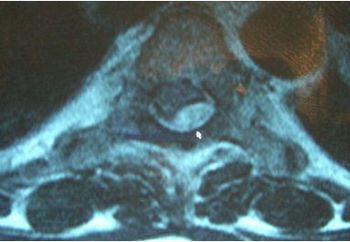

Images: Horner syndrome, neurofibroma, sciatica, ulnar neuropathy, intradural extramedullary schwannoma (neurinoma), moyamoya syndrome and stroke.

Spinal problems include epidural abscess, paravertebral muscle atrophy, Chiari I malformation, osteomyelitis/discitis, diastematomyelia, spinal compression, spinal tuberculosis.